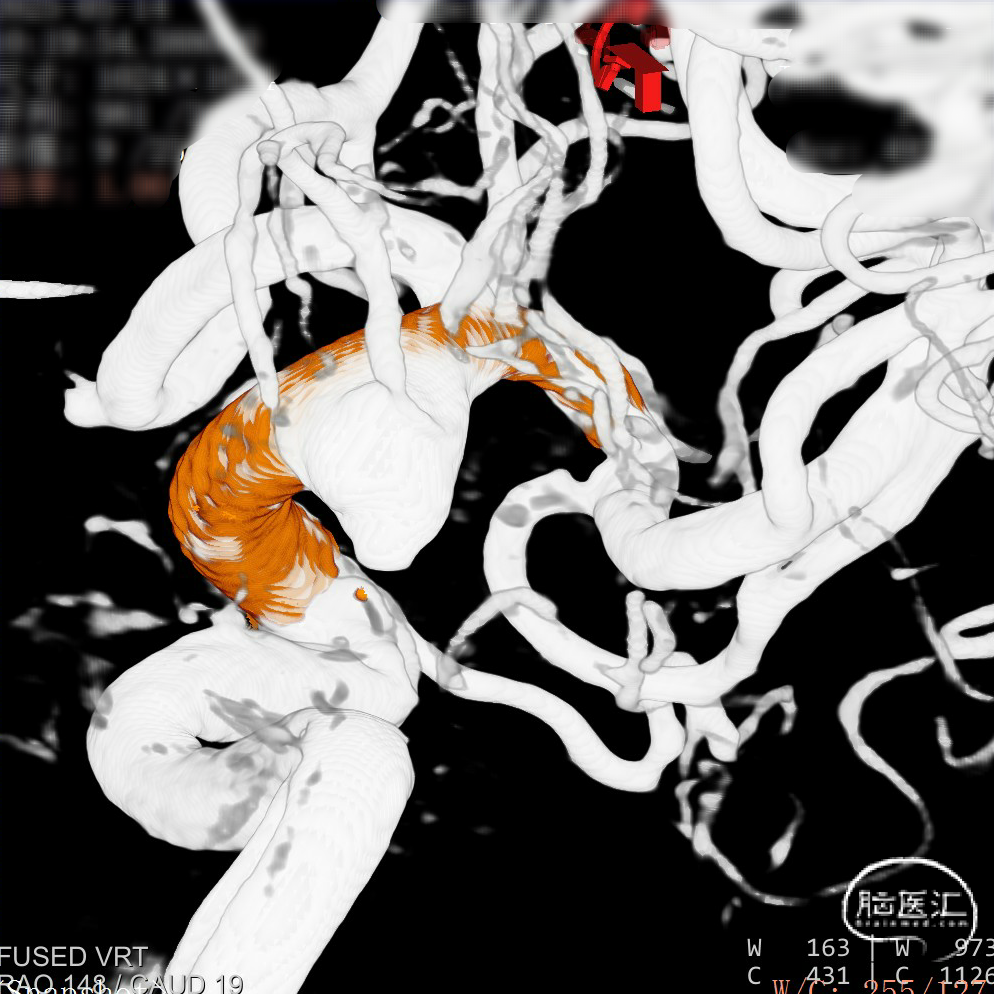

CTA:右侧颈内动脉C7段动脉瘤。

老年女性患者,检查发现右侧颈内动脉C7段大动脉瘤,动脉瘤直径大于10mm,形态不规则,宽颈,手术指征明确,既往高血压、肿瘤病史,首选微创介入手术,术中造影证实动脉瘤直径大于10mm,绝对宽颈,形态不规则,局部仔瘤改变,右侧脉络膜前动脉从瘤体发出;微创介入血流导向装置是较优选择。

Surpass Evolve 5*30mm 血流导向密网支架

支架完全释放。

造影明确打开贴壁满意。

正侧位造影:支架放置后可见动脉瘤内造影剂明显滞留。

大动脉瘤的微创介入栓塞治疗存在需要支架辅助,瘤颈处理困难、复发率高、费用高等难点;血流导向密网支架置入是较优选择,操作相对简单,不用填塞弹簧圈,完整覆盖瘤颈,远期明显降低再复发概率。本病例为右侧颈内动脉C7段累及脉络膜前动脉的大动脉瘤,该部位解剖结构复杂,周围血管分支多,在操作过程中要避免损伤正常血管,否则会引发严重脑缺血事件;其次,动脉瘤与脉络膜前动脉关系密切,既要处理好动脉瘤,又要保证脉络膜前动脉的血供不受影响,这对手术操作精度要求较高;再者,瘤颈的处理较为棘手,瘤颈较宽,传统弹簧圈栓塞难以达到理想效果,且容易复发。血流导向密网支架置入可解决这些问题,术前需借助3D-DSA,全面评估动脉瘤大小、形态、瘤颈宽度、与周围血管关系,制定精准手术方案。操作时,微导管的到位是关键一步,要在路径图引导下,小心、轻柔操作,避免刺激血管引发痉挛或动脉瘤破裂。释放支架过程中,要注意关注支架位置和贴壁情况。释放后要通过多角度造影,确认支架完全覆盖瘤颈,且支架内血流通畅,分支血管未受影响。同时,术后要密切观察患者神经功能变化,预防血栓形成、血管痉挛等并发症,及时给予抗血小板、解痉等药物治疗。

Surpass Evolve血流导向密网支架是专为颅内动脉瘤介入治疗设计的血流导向装置,采用钴铬合金编织网,金属覆盖率可达30-35%;头端易打开,具备优异的贴壁性,通过性优越,适合迂曲血管路径;多规格可选;适用于复杂型(大型、巨大型、梭形或宽颈)颅内动脉瘤。